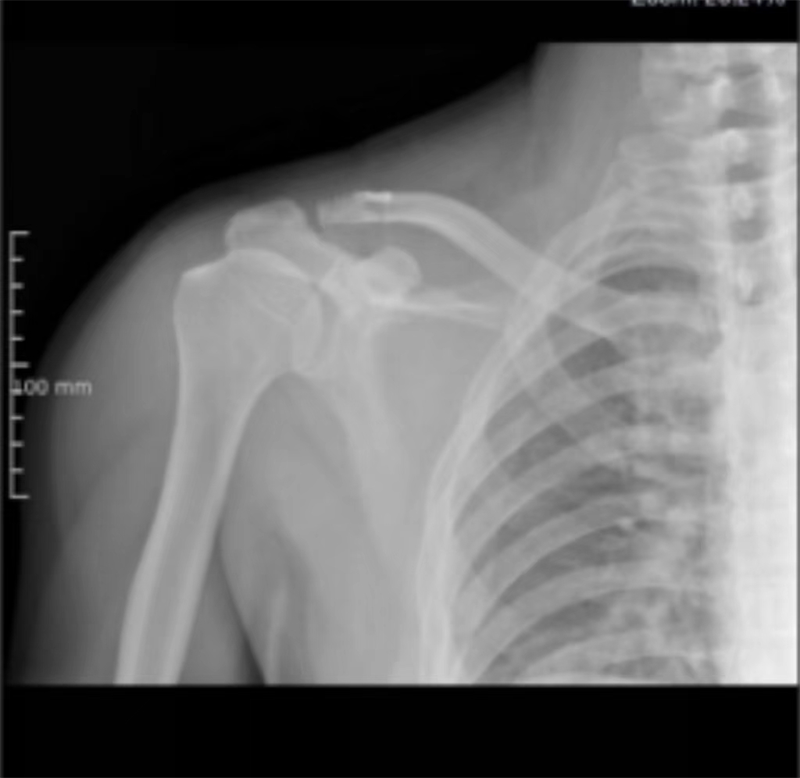

近期,寿光和信医院骨外科采取肩锁关节脱位切开复位袢钛板内固定术,一锚双袢固定,为肩锁关节脱位患者提供了一种全新的治疗选择。

肩锁关节脱位是创伤骨科的一种常见疾病,而肩锁关节脱位切开复位袢钛板内固定术则为这些患者带来了曙光。术后功能良好,肩锁关节脱位Ⅲ度新鲜损伤生物重建有优势,美容缝合,不用二期取出内固定,简单、实用、美观、功能良好,比钩钢板固定有很大优势。通过及时的治疗和正确的康复措施,患者完全可以告别肩锁关节疼痛带来的困扰,重新拥有健康和快乐的生活。